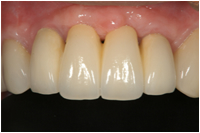

【審美総合:施術前】 【審美総合:施術後】

症例の説明

全体が歯周病でガタガタになっています。上顎の奥歯と下顎の全ての歯は抜歯せざるを得ませんでした。抜歯した部分にインプラントを埋め、歯周病の治療を行い、全体をセラミックで治療しました。下顎の歯は1本も残りませんでしたがインプラントを用いることでよく噛めるようになりました。